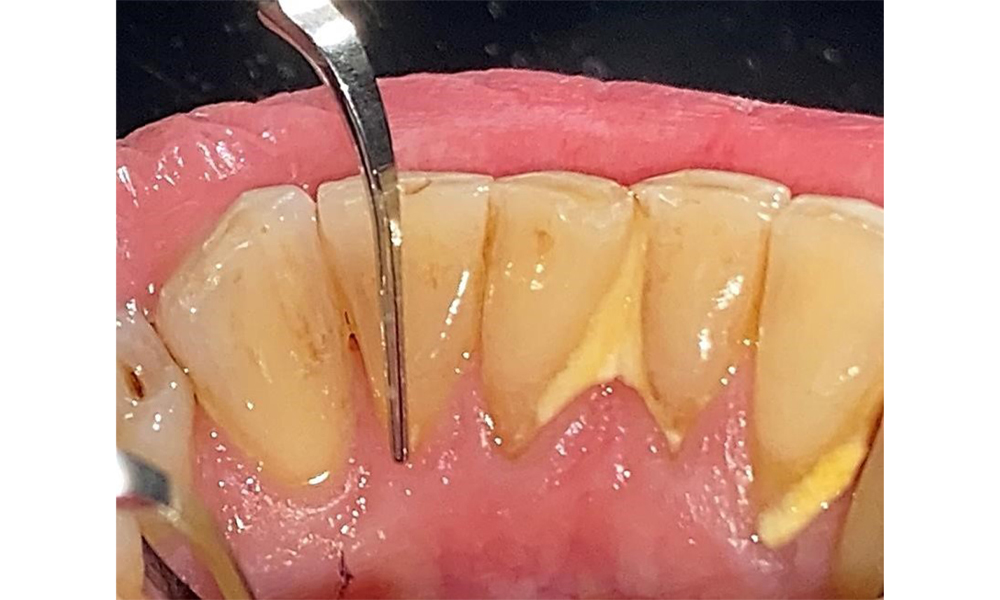

Pacientul prezintă boală parodontală în stadiul II, gradul B (5). Profunzimile clinice de sondare observate, între 1 și 3 mm, se încadrează în limitele fiziologice. Localizat, s-au observat profunzimi de 5 mm, la nivel meziopalatin, atât pe 17, cât și pe 27. Se constată recesiuni generalizate de 1-3 mm, cu pierderi parțiale ale papilelor interdentare (Fig. 2, Fig. 3, Fig. 4)

Nu există limitări în ceea ce privește alegerea metodelor de instrumentare. Sunt esențiale intervențiile subgingivale și supragingivale regulate, pentru prevenirea progresiei bolii - datorită parodontozei preexistente și a riscului ridicat de recidivă. Nu există limitări privind alegerea instrumentelor pentru îndepărtarea mecanică a biofilmului dintr-o perspectivă medicală generală, iar îndepărtarea trebuie efectuată în funcție de necesități. Placa dură și mineralizată, cum ar fi tartrul și concrețiunile, trebuie îndepărtate cu ajutorul pieselor de detartraj manuale sau al scalerului sonic/ultrasonic (Fig. 9) (8, 9).